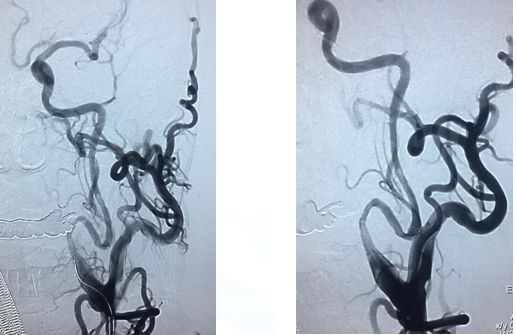

造影示:颈内动脉闭塞,眼动脉有代偿,血管闭塞原因决定血管再通方式!

找到闭塞血管部位,狭窄?夹层?

在颈内远端用6*30Solitaire逐次向近端释放支架(夹层可能性大)

支架释放状态血管通畅,逐渐找到血管闭塞部位

支架在病变最近端释放

11-3,21:40:血管再通,支架释放解脱